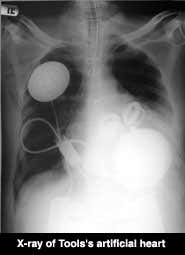

It has been 51 days since surgeons Laman Gray and Robert Dowling replaced Tools’s heart with an artificial heart in a 10 hour operation on 2 July in the Jewish Hospital at Louisville, Kentucky.

Photo: Jewish Hospital, Kentucky

The heart, made by Massachusetts-based company Abiomed, is powered by a 450 gram internal battery implanted in Tools’ rib cage. It can be recharged across his skin by a 900 gram booster battery that he carries around under his shirt. Without the booster, the internal battery lasts just 30 minutes, enough time to take a short walk or a shower.